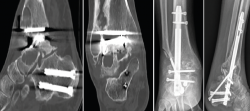

Se reintervino al paciente realizando la extracción del fragmento distal del clavo con el sistema extractor del mismo. Para la extracción del extremo proximal fue necesario, además de la utilización de las guías curvadas, abordar el foco de la pseudoartrosis hasta visualizar el clavo y, con una fresa de alta velocidad, hacer una muesca en el mismo. Mediante la percusión sobre un escoplo apoyado en la muesca realizada en el clavo y con la ayuda de las agujas guía introducidas a través del clavo, se consiguió la extracción del extremo proximal a través de la planta del pie (Figura 3). Se legró la superficie articular tibiotalar y se colocó injerto de cresta ilíaca, fijando la artrodesis con una placa TTC (Palex Medical), aunque la articulación subtalar estuviese artrodesada, para dar mayor solidez al montaje.

Figura 3. Imágenes del clavo tibiotalocalcáneo roto a través de la trinchera ósea y maniobra de extracción con guías endomedulares ayudadas por la impactación directa en la muesca realizada en el clavo.